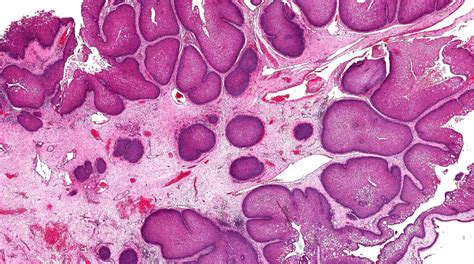

Diagnosing warts in the nose typically involves a physical examination by a healthcare provider. The doctor may use a magnifying glass or a special light to get a better view of the nasal cavity. In some cases, a biopsy may be performed to confirm the presence of HPV and rule out other conditions.

• papilloma inside nose